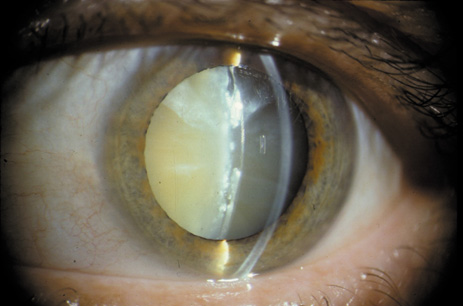

One can examine this type of cataract with direct illumination, using the narrow and broad beams of the slit-lamp to show the characteristic granular inner surface immediately in front of the posterior capsule (Fig. 13). The problem with this technique, however, is that patients may not tolerate any prolonged direct illumination because of the glare. Retroillumination is therefore more useful for revealing the outline of the opacity, since it is usually seen as an “island” in the center of the posterior capsule, which is further highlighted by the shadow cast by the opacities.33 However, in the early stages of this type of cataract, the dust-like particles that might be noticeable in the central posterior subcapsular area with direct illumination disappear or are difficult to see with retroillumination (Fig. 14). Eventually this “dusting” becomes dense enough to cast a shadow and thus appear on retroillumination. The smooth orange background of the fundus helps to highlight the rough, irregular pseudopodia-like edges of the central opacity. In advanced stages, the PSC may become a thick, calcified plaque (Fig. 15). During surgery, excessively vigorous scraping or vacuuming of the calcified opacity can lead to rupture of the posterior capsule. Usually, small remnants that are left behind after surgery are reabsorbed and do not interfere with vision; otherwise, they are easily treated with a neodymium : yttrium (Nd:YAG) aluminum garnet laser. Pathologic evidence suggests that most PSCs result from the migration of bow region cells into the potential space (along with accumulated cellular debris) between the posterior capsule and the cortex.34–36

Fig. 13. Direct slit-lamp illumination of a PSC, showing an irregular granular surface in front of the posterior capsule.

Fig. 14. A PSC, showing vacuoles and dust-like material in the potential space between the posterior cortex and the capsule.

Fig. 15. Example of an Oxford camera retroillumination image of a PSC, and the automated method used to measure the area of cataract.